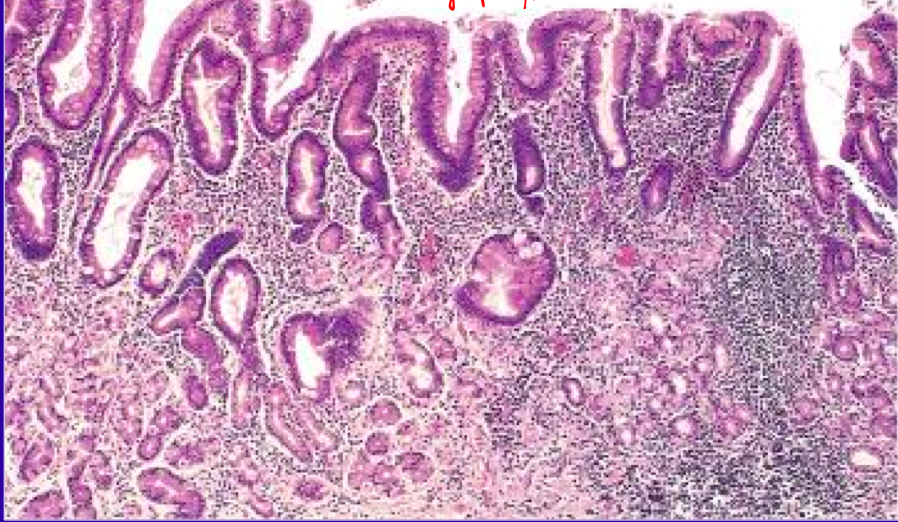

<p>What is the diagnosis of the stomach biopsy? Key feature?</p>

<p>chronic gastritis</p>

<ul>

<li>key feature is the lymphocytic infiltration</li>

</ul>